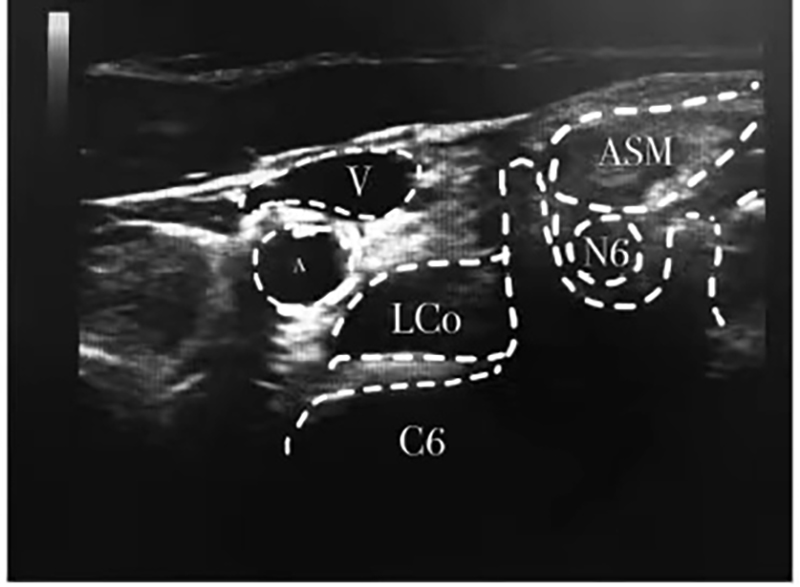

由于患者已嘗試了一般療法、藥物治療和經(jīng)穴治療,均未能阻止其打嗝,并持續(xù)7日,最后在醫(yī)師的推薦下,由麻醉科為其進(jìn)行“超聲引導(dǎo)下膈神經(jīng)+星狀神經(jīng)節(jié)阻滯”治療。

麻醉科童主任說:膈神經(jīng)阻滯治療頑固性呃逆主要是通過阻斷呃逆的反射弧,減低膈神經(jīng)應(yīng)激性,達(dá)到終止呃逆的目的。星狀神經(jīng)節(jié)阻滯治療頑固性呃逆其機(jī)制是通過藥物擴(kuò)散,阻斷頸胸交感神經(jīng)節(jié)前和節(jié)后纖維,抑制交感神經(jīng)支配的組織器官的交感活動(dòng)效應(yīng),干擾膈神經(jīng)沖動(dòng),同時(shí)亦能調(diào)理下丘腦和植物神經(jīng)功能,改善由于植物神經(jīng)功能紊亂引起的膈肌痙攣狀態(tài)。能起到立竿見影的作用。